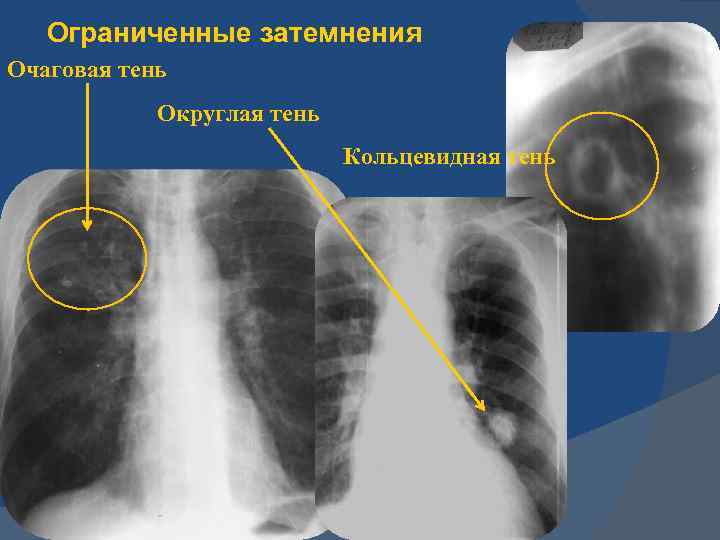

Иллюстрации по теме очагового и инфильтративного туберкулеза